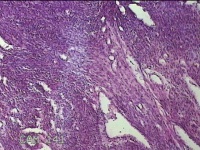

子宫肌瘤

性别

女

年龄

41岁

临床诊断

子宫肌壁间肌瘤

一般病史

发现子宫肌瘤4年余。

标本名称

大体所见

灰白色圆柱形条索状组织10.5x7x1.3㎝一堆,切面均为灰白色结节状或编织状,质硬。

图4